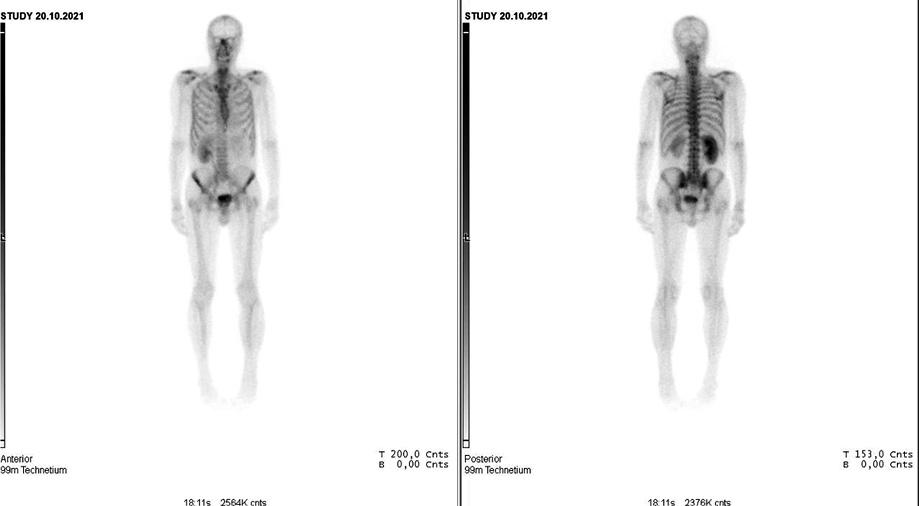

Рис. 5. МРТ ОМТ от 27.12.2021 в сравнении с МРТ от 24.03.2022. Состояние после 6-го курса лекарственного лечения по схеме EP: отсутствие опухолевого роста.

Fig. 5. Pelvic MRI dated 27.12.2021 in comparison with MRI dated 24.03.2022. State after the 6th course of drug treatment according to the EP regimen: no tumor growth.

В июне 2022 г. выполнено контрольное обследование, МРТ ОМТ: на полученных МРТ в сравнении с обследованием от 24.03.2022 без существенной динамики. Пациент оставлен на МХТ препаратом этопозид (рис. 6).

Рис. 6. МРТ ОМТ от 07.06.2022. Состояние после 6-го курса лекарственного лечения по схеме EP. Cостояние в процессе МХТ препаратом этопозид.

Fig. 6. Pelvic MRI dated 07.06.2022. State after the 6th course of drug treatment according to the EP regimen. Monochemotherapy with etoposide is ongoing.

По результатам контрольного обследования от августа 2022 г. (МРТ ОМТ от 18.08.2022): в сравнении с данными от 07.06.2022 отмечается картина отрицательной динамики в отношении появления по задне-правой стенке мочевого пузыря на расстоянии до 11 мм от уретры узлового образования округлой формы с бугристыми контурами, с истинным ограничением диффузии и интенсивным контрастированием, размерами до 6×6 мм; характер роста образования смешанный; наружный контур стенки четкий ровный (рис. 7).

Рис. 7. МРТ ОМТ от 07.06.2022 в сравнении с МРТ ОМТ от 18.08.2022. Состояние после 6-го курса лекарственного лечения по схеме EP. Cостояние в процессе МХТ препаратом этопозид: появление узлового образования округлой формы с бугристыми контурами.

Fig. 7. Pelvic MRI dated 07.06.2022 in comparison with pelvic MRI dated 18.08.2022. State after the 6th course of drug treatment according to the EP regimen. MCT with etoposide is ongoing. A rounded nodule with bulging contour appeared.